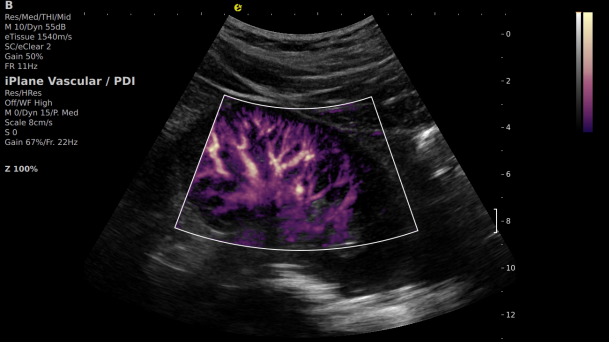

在肾移植领域,医生最怕的不是手术刀下的惊心动魄,而是那些手术后肉眼看不见的危机——急性排斥反应导致的血小板聚集形成的微血栓、毛细血管网损伤等...这些“隐形杀手”曾让无数移植肾在悄无声息中衰竭。而逸超医疗(ESI)的iPlane Vascular平面波超微细血流显像技术,正是为破解这一难题而生。

【黑科技登场】

开启移植肾的"微观视界"

这项革命性技术通过三大创新实现质的飞跃:

1) 基于OmniSound®平面波超快速平台,超声信号采集帧频提高了200倍(25000Hz)。

2) 可检测20-50μm级细小血管低速血流信号,能看清头发丝1/2粗细的微血管;

3) 通过血管指数(VI)定量评估局部血管密度,以定量化数据实时监测血流灌注情况,预判肾功能恢复情况;

超微视血流显像显示肾脏五级血管

微米级超高分辨率血流信号显像

肾脏的灌注评估,RI/VI量化数据

超微视血流显像评估肾移植术后灌注情况

这一项无创、无辐射操作简便且无需造影剂的黑科技,相当于用"高速摄像机"记录血液细胞的运动轨迹,让血管并发症"无处遁形。

从术前评估到术中到术后,再到终身监护,当20-50μm级的超微血流信号在屏幕上跳动,我们看到的不仅是技术的精进,更是生命的律动。iPlane Vascular正在重新定义肾移植监护的标准——让医生拥有了"显微视力",让每一个微小血管的异常都无所遁形,让每一次免疫排斥的萌芽都被及时扼制。